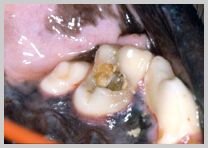

Teeth Destroyed by Disease

Teeth ruined by advanced caries, feline neck lesions etc.

should be considered for extraction.

Advanced feline odontoclastic resorptive lesion on buccal

surfaces of 409 and 407